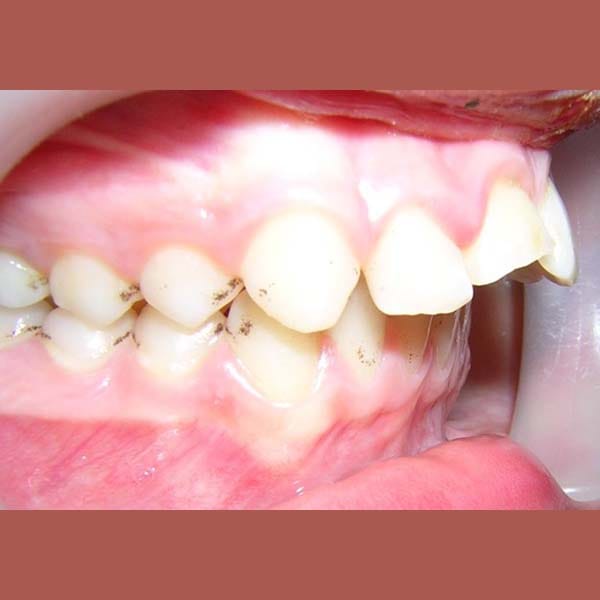

كما تظهر الصور، كان التحسن جذرياً ليس فقط في الابتسامة ولكن في تناسق ملامح الوجه بالكامل. تم تصحيح البروز، وتحسنت علاقة الفكين، وحصلت صديقتنا الصغيرة على ابتسامة جميلة وواثقة.